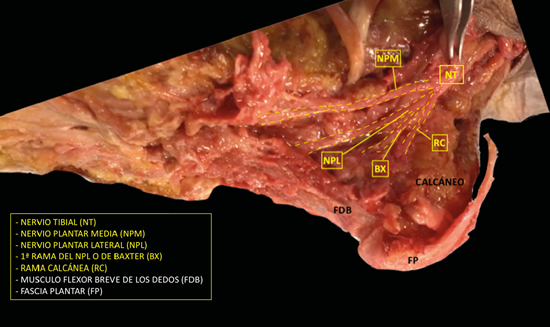

El nervio tibial, en su tránsito por la cara medial del tobillo y del pie, dará las ramas calcáneas mediales, el nervio plantar medial, el nervio plantar lateral y la primera rama del nervio plantar lateral o rama de Baxter3. El nervio peroneo profundo se localiza en profundidad a la musculatura extensora del primer radio a la altura del tobillo. El nervio peroneo superficial discurre por el borde anterior del peroné para llegar escindido al tobillo en los nervios cutáneo dorsal medial y cutáneo dorsal intermedio. El nervio sural, situado en el aspecto posteromedial de la pierna adyacente a la vena safena menor, dará las ramas calcáneas laterales antes de girar retromaleolar al peroné hacia el pie para denominarse como el nervio cutáneo dorsal lateral (Figuras 2 y 3)2,3.

Figura 2. Imagen de disección del nervio tibial y sus ramas.